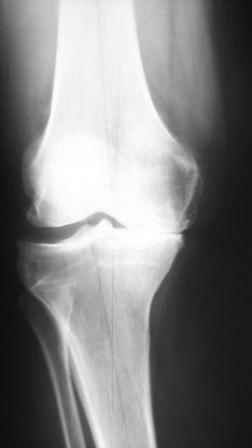

вообще, то в комплекс симптопатической терапии входят всякие медикаменты + ИСЖ (гиалуронаты) + гормоны при "мокром" суставе + физиолечение + грязи + солнце - воздух и вода + доброе слово и участие доктора и все это.... не удел ортопеда -хирурга. Это ближе к терапии. Чуть агрессивнее различные артроскопические санации и манипуляции - временно помогает + ИСЖ + фиксаторы + ортезы + аппараты + трость и костыли + коляска. Однако судя по рентгенограммам - суставы приговорены к эндопротезированию.

Глядя на снимки, кроме оперативного лечения в голову ничего не приходит. Хотя бы корригирующая кортикотомия б/б кости с минимальной внешней фиксацией. Высылаю пример.

Откровенно говоря, прочитав ваше суждение по теме о возможности неоперативного лечения двустороннего гонартроза, варусной деформации,сильно

Каждому методу свое время и место. у обсуждаемого пациента очевидна перегрузка медиальных отделов суставов с разрушенными суставными поверхностями, каким образом, вы представляете себе облегчить боли НПВП (разнообразие которых столь велико, что больному не хватит жизни и здоровья, чтобы все перепробовать, но идля *участливого* доктора всегда есть путь к отступлению - не помогает один, давайте попробуем другой - бесконечный,